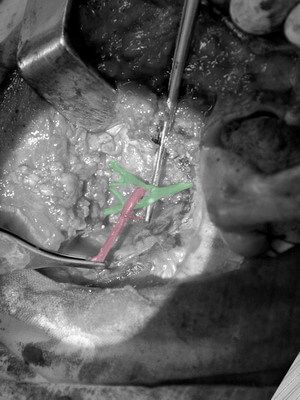

Пациент обратился в клинику с жалобами на дискомфорт левой околоушной области. По данным КТ и пункционной биопсии поставлен предварительный диагноз - смешанная опухоль околоушной слюнной железы. Образования данной локализации являются условно злокачественными, склонными к частым рецедивам, поэтому рекомендуются к радикальным эксцизиям. Особенностью топографии данного органа является прохождение всех веток лицевого нерва через железу, в том числе и через опухоль., косметическим доступом произведено удаление поверхностной доли околоушной железы, с образованием, удаление регионарных лимфоузлов. Данная методика является органосохраняющей, операция начинается с выделения (диссекции) лицевого нерва (помечен "зеленым цветом"), а уж потом удаления опухолевого слоя. На промежуточных фото виднеется временный парез краевой ветки n.facialis, которая потом полностью восстановилась. Данная операция так же возможна с применением нейромониторинга лицевого нерва, что еще уменьшает риски повреждения нерва.